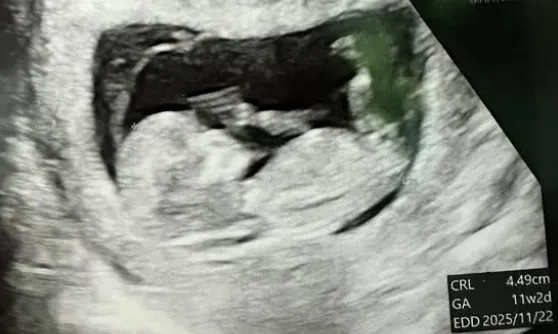

트루디는 지난 9일 자신의 인스타그램에 “지금도 믿기지 않지만, 제가 올해 11월에 엄마가 된다”라며 태아 초음파 사진을 공개했다.